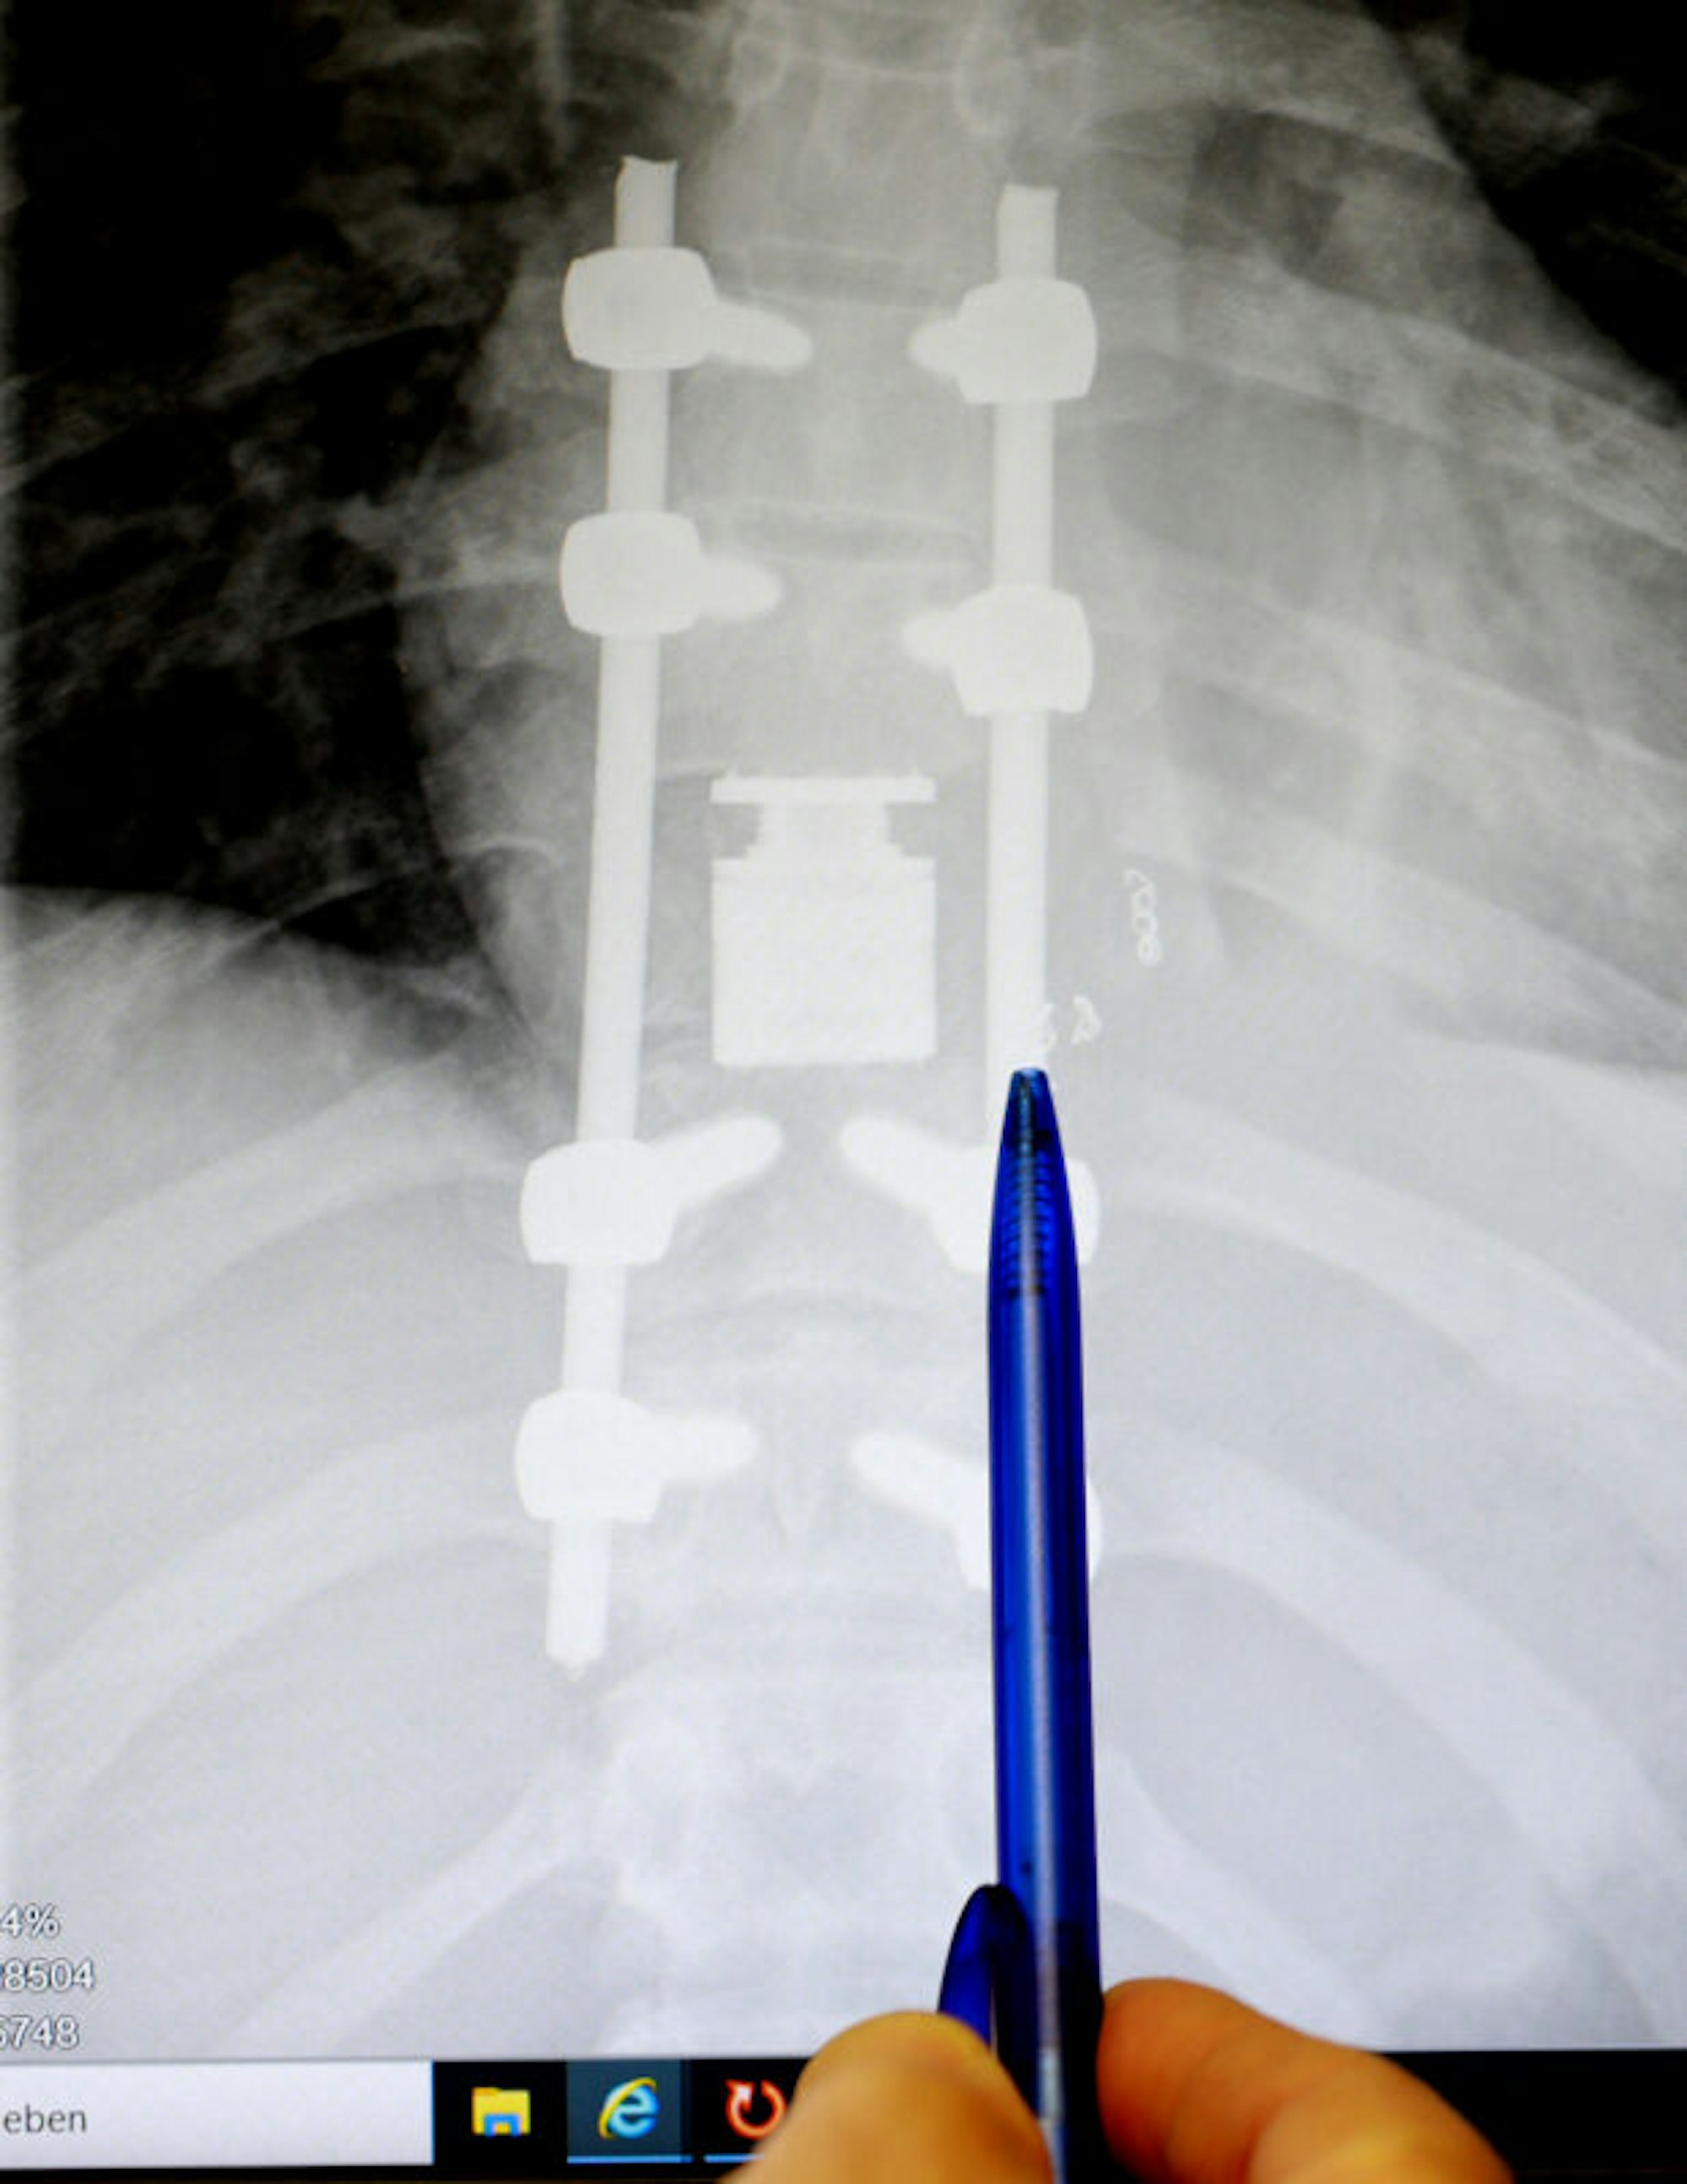

Der kranke Wirbel wurde durch einen Cage (Bildmitte) ersetzt

Die erste Diagnose: Skoliose, eine Verkrümmung der Wirbelsäule. Die junge Bosnierin bekommt Reha, doch danach ist ihr Zustand eher schlechter, mehrfach fällt sie beim gehen einfach um. Dann wird der Tumor gefunden: Ein Wirbelkörper ist von einem gutartigen Tumor befallen, der die Wirbelsäule krümmt und auf das Rückenmark drückt. 2018 wird Edna in Belgrad operiert und ein Teil des Tumors entfernt. Danach geht es ihr besser, sie kann wieder richtig laufen, doch der Tumor ist noch da – und wächst wieder.

Auf vier Operationen wurde der Eingriff verteilt, um den Blutverlust in Grenzen zu halten. Dabei wurde der vom Tumor befallene Wirbel entfernt und durch einen sogenannten „Cage“, einen expandierbaren Wirbelkörperersatz ersetzt. Dieser musste am Rückenmark vorbeigeschoben werden, ein heikler Eingriff.